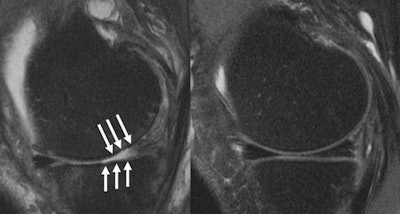

MRI images of a knee joint of a patient showing (left) severe cartilage defects compared to a patient with an intact knee joint. Image courtesy of Upadhyay Bharadwaj, MD